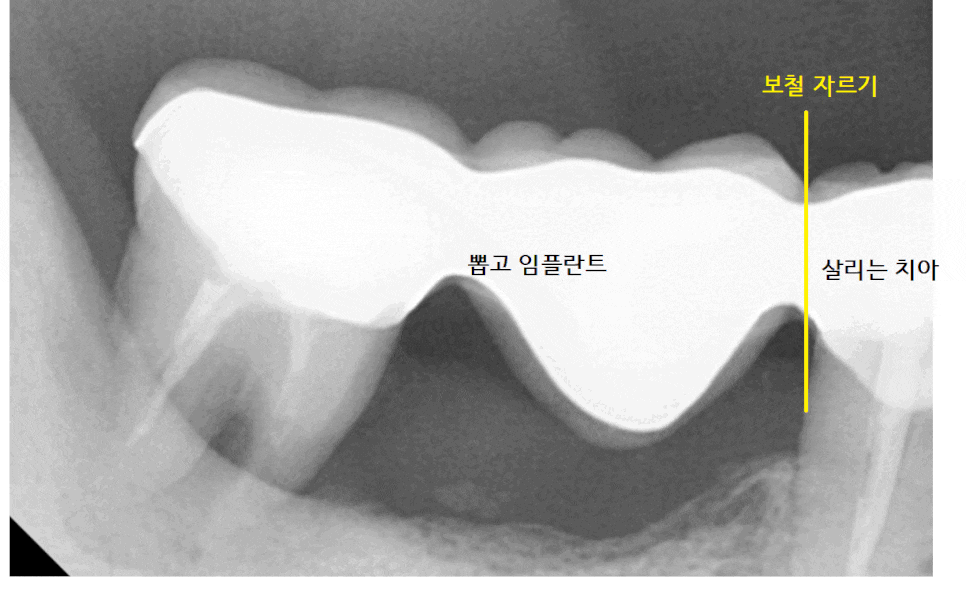

3개의 보철 중

작은 어금니 치아는 살려볼 수 있었는데요.

자연 치아가 1개라도 더 있으면 유리하기 때문에

오래된 브릿지를 잘라서

부분 임플란트 하기로 상담해 드렸습니다.

결국 브릿지 연결되어 있던 것을 잘라서

앞에 치아는 살리고

뒤에 치아는 뽑는 것으로

강일역 치과에서 임플란트를 진행했습니다.